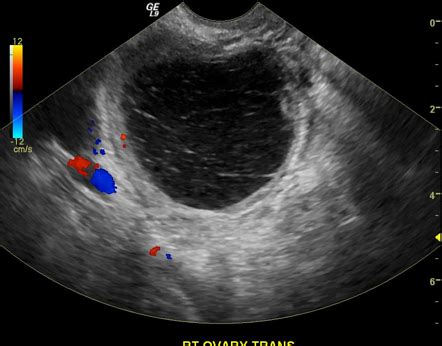

The diagnosis of a hemorrhagic ovarian cyst typically involves a combination of physical examination, medical history, and imaging tests. A pelvic exam may reveal a tender, palpable mass in the pelvic region. Ultrasound, computed tomography (CT), and magnetic resonance imaging (MRI) scans can help confirm the presence of a hemorrhagic ovarian cyst and determine its size, location, and potential impact on surrounding tissues.

+A hemorrhagic ovarian cyst is typically diagnosed through a combination of physical examination, medical history, and imaging tests, including ultrasound, computed tomography (CT), and magnetic resonance imaging (MRI) scans.